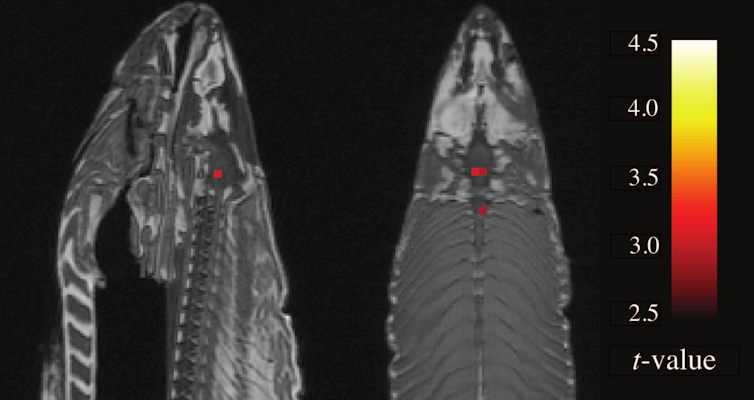

This a functional magnetic resonance imaging (fMRI) experiment. As you play, a massive magnetic field pulsates through your body and picks up minute changes in the blood flow of your brain.

The pattern of changes differs when you believe you play a person as opposed to when you believe your opponent is a computer.

Subtract the patterns from each other, do some more statistics, and the result is a neat coloured blob on a picture of the brain.

Since the only real difference between the playing conditions is your mental state, the difference in brain activity must be specific to that type of mental state.

So the blob signifies the part of the brain that explains why we interact differently with people and computers.